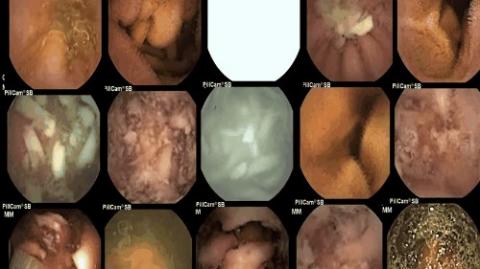

Để thực hiện nghiên cứu này, bác sĩ Kuo đã sử dụng một chiếc máy quay có kích cỡ chỉ bằng viên thuốc để tìm hiểu những gì đang thực sự diễn ra bên trong dạ dày của người sau khi ăn mì.

Trong thí nghiệm này, một người sẽ ăn mì ăn liền và người còn lại ăn mì tươi - một loại mì được làm từ bột và trứng, không sử dụng chất phụ gia.

Nhưng sau khoảng 20 phút, sợi mì ăn liền vẫn còn gần như nguyên vẹn trong bộ máy tiêu hóa của chúng ta. Hình dáng sợi mì ăn liền nguyên sợi (bên trái) trong khi phần sợi mì tươi bắt đầu có dấu hiệu tan rã.

Tuy nhiên, điểm bất ngờ là sau khoảng 2 giờ đồng hồ, những sợi mì ăn liền vẫn nguyên sợi (hình trái) trong bộ máy tiêu hóa. Điều đó cho thấy, mì ăn liền thực sự khó tiêu và ảnh hưởng lớn tới sự hấp thu dinh dưỡng của chúng ta.